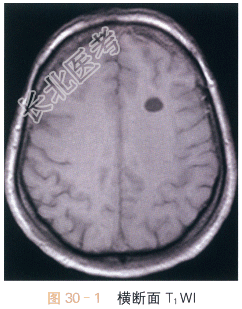

女,28岁,头痛、头晕4月余。

读片分析:头颅横断面T₁WI,T₂WI显示左侧额叶均匀的长T₁WI,长T₂WI信号,边界清晰,周围脑实质未见水肿;横断面、矢状面T₁W增强显示左侧额叶病灶未见明显强化。结合病史,患者考虑为神经上皮囊肿。